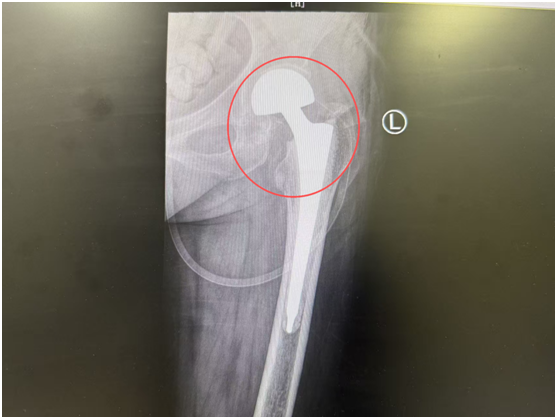

术后

考虑到刘奶奶的复杂病情,骨科一病区团队迅速组织多学科会诊,邀请内分泌科医生介入,通过胰岛素泵精准调控血糖,还指导刘奶奶进行踝泵训练、股四头肌等长收缩等康复锻炼,为手术筑牢基础。待刘奶奶血糖平稳、身体状况达到手术条件后,由骨科一病区杨鹏主任主刀,为她顺利实施了关节置换手术。

术后第一天,刘奶奶的疼痛症状就有了明显改善,已经能够在辅助下下地行走,成功规避了长期卧床可能引发的肺部感染、血栓、压疮等风险。